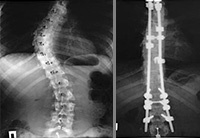

Александре 15 лет, она из г. Обнинск Калужской области. Александра ребенок-инвалид, страдает тяжелейшим заболеванием позвоночника. Её диагноз – правосторонний грудной сколиоз 4 степени. В Калужской областной детской больнице ей должны установить имплантаты стабилизации позвоночника Medtronic (США). Оплата имплантатов за счет бюджетных средств не производится. Стоимость базовой комплектации имплантатов 318 200 рублей.